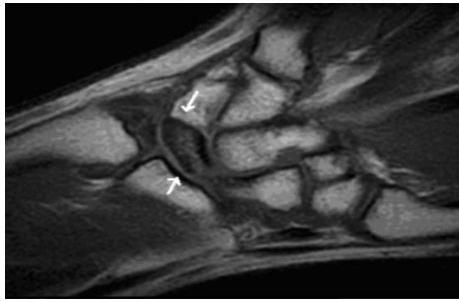

¿QUÉ ES LA ENFERMEDAD KIENBÖCK? - P.52